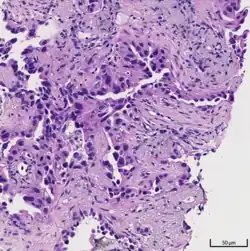

Histopathology of lepidic predominant adenocarcinoma.

Acinar pattern.[16]

Solid pattern.[17]

• lepidic predominant[18]

• acinar predominant[19]

• papillary predominant[20]

• micropapillary predominant[21]

• solid predominant with mucin production[22]

Cell patterns identifying subtypes are associated with prognosis, ranging from favorable (lepidic) to intermediate (acinar and papillary) to poor (micropapillary and solid).[2]

Adenocarcinoma of the lung tends to stain mucin positive as it is derived from the mucus-producing glands of the lungs. Similar to other adenocarcinoma, if this tumor is well differentiated (low grade) it will resemble the normal glandular structure. Poorly differentiated adenocarcinoma will not resemble the normal glands (high grade) and will be detected by seeing that they stain positive for mucin (which the glands produce). Adenocarcinoma can also be distinguished by staining for TTF-1, a cell marker for adenocarcinoma.[29]

As discussed previously, the category of adenocarcinoma includes are range of subtypes, and any one tumor tends to be heterogeneous in composition. Several major subtypes are currently recognized by the World Health Organization (WHO)[1] and the International Association for the Study of Lung Cancer (IASLC) / American Thoracic Society (ATS) / European Respiratory Society (ERS):[30][31][32] lepidic predominant adenocarcinoma, acinar predominant adenocarcinoma, papillary predominant adenocarcinoma, micropapillary predominant adenocarcinoma, solid predominant adenocarcinoma, and solid predominant with mucin production. In as many as 80% of these tumors, components of more than one subtype will be recognized. Surgically resected tumors should be classified by comprehensive histological subtyping, describing patterns of involvement in increments of 5%. The predominant histologic subtype is then used to classify the tumor overall.[2] The predominant subtype is prognostic for survival after complete resection.[33]